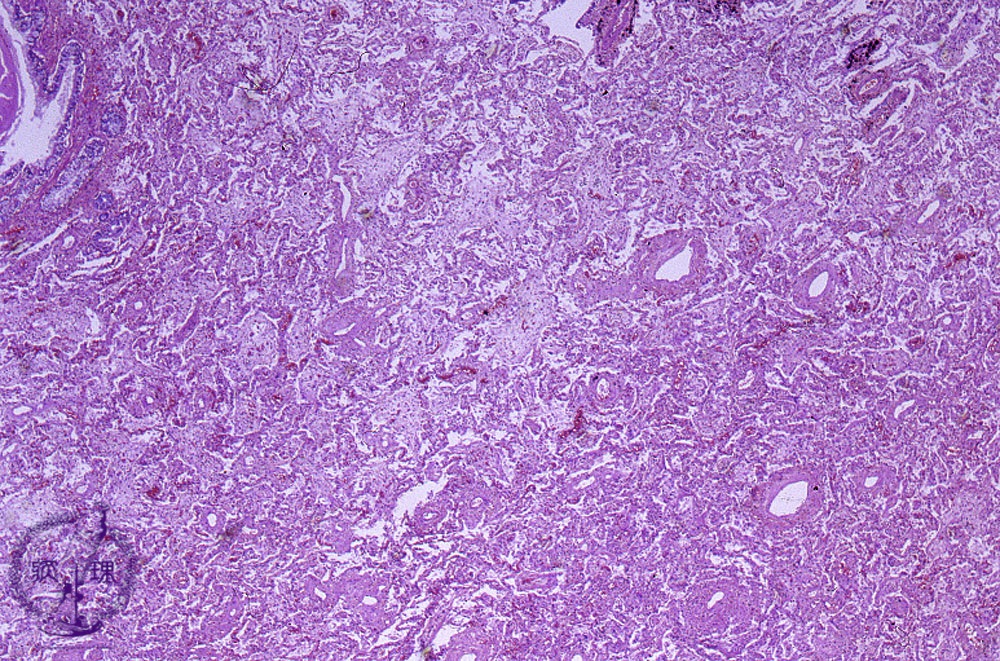

- (13)Organizing pneumonia

Microscopic view (HE stain, low power view): As bronchopneumonia resolves and heals, exudative materials are dissolved, removed or absorbed; however, the latter deposits may occasionally remain unresolved for poorly understood reasons. Consequently, phagocytic macrophages are prompted to marginate from interalveolar capillaries, immature fibroblasts proliferate and an alveolar membrane forms.